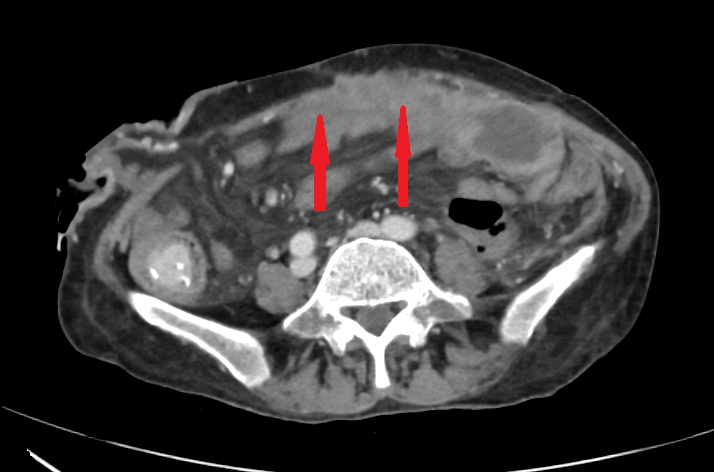

Contrast-enhanced CT of the abdomen, revealing air in intrahepatic biliary tree (pneumobilia) (red arrow)